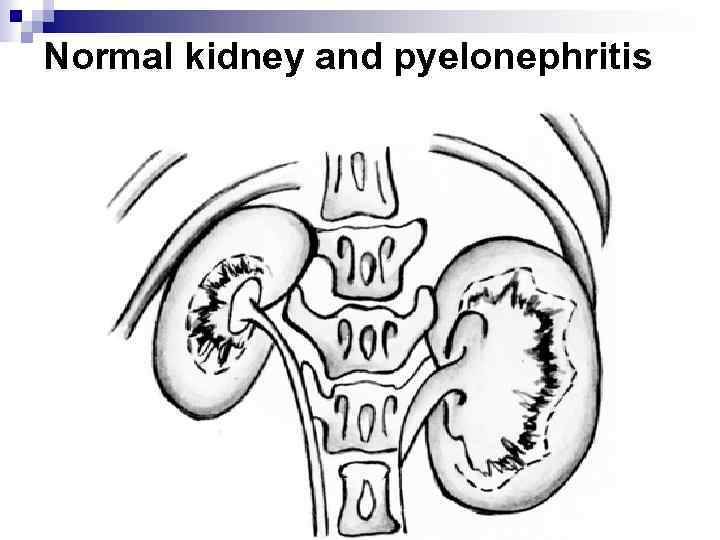

Normal kidney and pyelonephritis

Normal kidney and pyelonephritis